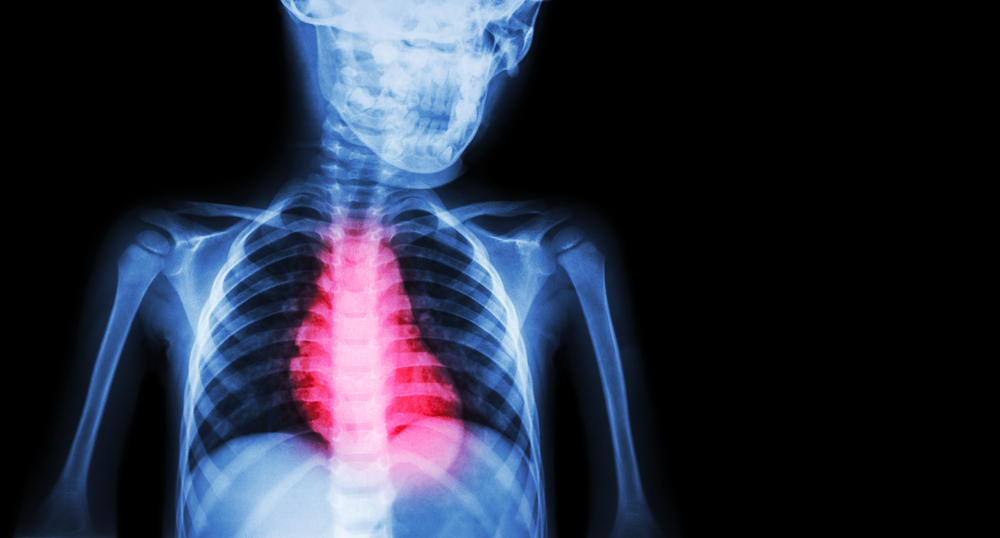

Nors simptomai dažnai primena kitus širdies smūgio tipus, NSTEMI ir STEMI skiriasi pagal tam tikrus širdies elektrinės veiklos bruožus. Vertinant širdies veiklą elektrokardiogramoje (EKG), abu infarktų tipai rodo akivaizdžių skirtumų.

- NSTEMI metu EKG galima stebėti sumažėjusią ST bangą arba pasikeitusią T bangą, tačiau Q banga neatsiranda.

- Dažniausiai šis tipas rodo tik dalinį širdies kraujagyslės užsikimšimą.

- STEMI atveju EKG matoma ST segmento pakilimas, būdingas visiškai užsikimšusiai vainikinei arterijai.

Nustatyti NSTEMI padeda kraujo tyrimai ir EKG. Tyrimai dažniausiai parodo padidėjusias širdies pažeidimą rodančias medžiagas, tokias kaip CK-MB, troponinas I ir troponinas T. Šių medžiagų lygis paprastai būna ne toks aukštas kaip kito tipo infarkto atvejais.

Galutinę diagnozę patvirtina EKG, kuri leidžia išsiaiškinti, ar iš tiesų įvyko širdies smūgis, ir nustatyti jo tipą pagal širdies elektrinio aktyvumo pokyčius.